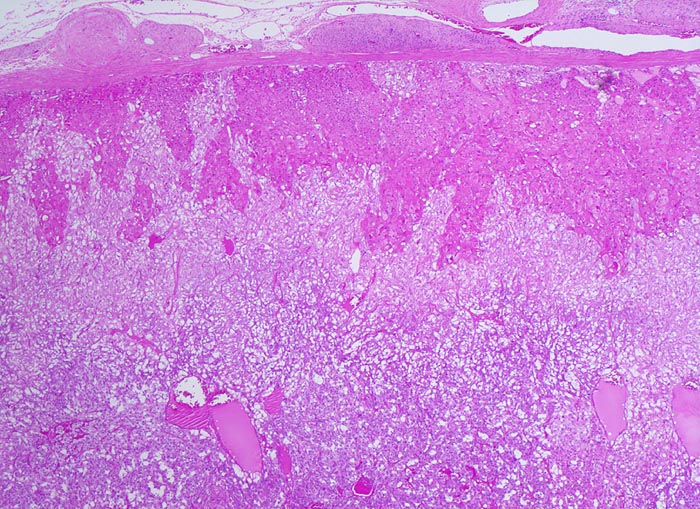

• Unscharf begrenzter, gefässreicher Tumor ausgehend vom Nebennierenmark.

• Zungenförmige Infiltration der angrenzenden Nebennierenrinde. Die Zellen der Nebennierenrinde haben reichlich eosinophiles Zytoplasma und kleinere Kerne als die Tumorzellen.

• „Zellballen“ umgeben von schmalen Bindegewebssepten mit kapillären Gefässen.